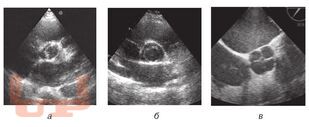

В книге нашли отражение современные способы диагностики пороков сердца, прежде всего с помощью эхокардиографического метода.